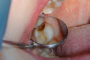

فلیپر دندان یا همان دندان مصنوعی فلیپر یک نوع پروتز موقت و متحرک است که معمولاً برای جایگزینی یک، دو یا نهایتا سه دندانی که به هر دلیل افتاده، استفاده میشود. این پروتز از پایهای سبک و نازک که اغلب از جنس آکریلیک است، ساخته میشود که دندانهای مصنوعی روی آن قرار گرفته و به کمک گیرههای ظریف یا طراحی خاص، به دندانهای مجاور متصل میشود. هدف اصلی از استفاده فلیپر، پر کردن موقت فضای خالی دندانها تا زمان انجام درمان دائمی مانند ایمپلنت یا بریج است.

در واقع، فلیپر نوعی «پل موقت» بین از دست دادن دندان و جایگزینی دائمی آن محسوب میشود. بسیاری از بیماران پس از کشیدن دندان، باید چند ماه صبر کنند تا لثه و استخوان فک بهبود پیدا کند و برای درمان قطعی آماده شوند. در این فاصله، استفاده از فلیپر کمک میکند تا لبخند طبیعی باقی بماند، صحبت کردن روانتر شود و جویدن غذاها آسانتر گردد.